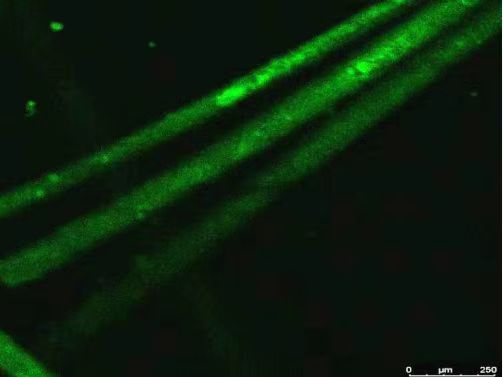

一等奖作品:《相遇》

作者:汪文倩、王洋、屈莉莉;指导老师:刘夫锋

科学意义:帕金森病模型线虫 A30P 模拟了人体遗传因素导致的帕金森病。本图片采用的帕金森模型线虫A30P转入了人的α-突触核蛋白,在8个多巴胺神经元中可以检测到 Pdat-1: : EGFP 荧光。

图片创意:深海神秘幽深环境中,无法看清周围的事物,很容易迷失方向。一只海洋生物散发着明亮的光芒划破黑暗,与同伴相遇,相互支持、相互保护。从此在这黑暗中成为彼此的“指路灯”,照亮共同前进的路。在求学和科研路上目标明确的我们一同追光而行、坚持不懈、恪守原则,互相欣赏、互帮互助,披荆斩棘、乘风破浪、拼搏进取。